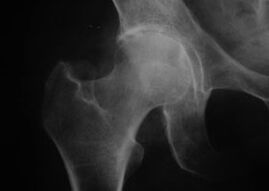

Aspecto de una articulación con artrosis

La principal causa de cambios patológicos son los trastornos metabólicos en el cartílago. La violación del trofismo del cartílago conduce a una pérdida irreversible de proteoglicanos y pérdida de elasticidad del tejido.

Los cambios distróficos en el cartílago implican cambios patológicos en la estructura de las superficies articulares de los huesos. Con el tiempo, el proceso de degeneración se extiende a los tejidos periarticulares.